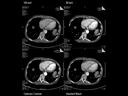

More and more radiologists are relying on the rich diagnostic possibilities offered by True Dual Energy imaging on Siemens Healthineers' CT scanner fleet ranging from SOMATOM® Scope Power up to the outstanding SOMATOM Force.

The question is: What makes True Dual Energy stand out? Look for these three criteria: crisp images with the option for even sharper contrast and significant artifact reduction; no extra dose in either Single Source or Dual Source Dual Energy scans, and a broad applicability for virtually all clinical questions and patients.

Discover Dual Energy (DE) spectral imaging. It’s the difference between images and answers. Visualization and characterization. Qualification and quantification. Built into all of our CT scanners, it delivers powerful performance, incredible versatility for your entire patient population, and exceptional ease-of-use – all while integrating seamlessly with your current workflow.